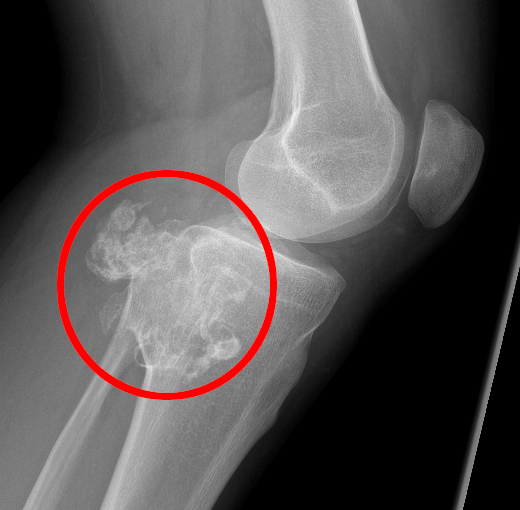

Condrosarcoma

- Descrizione: Il condrosarcoma è un raro Tumore Maligno dell'osso che origina dalla Cartilagine. Il sintomo più comune dell'affezione è rappresentato dal Dolore. I condrosarcomi primari insorgono da un piccolo gruppo di cellule cartilaginee; i secondari si sviluppano lentamente da un precedente tumore benigno della cartilagine.

- Foglietto embrionale: Mesoderma recente. In Fase attiva si ha necrosi del tessuto cartilagineo, con la formazione di buchi. In Fase di riparazione si ha ricostruzione tissutale a volte abnorme od eccessiva